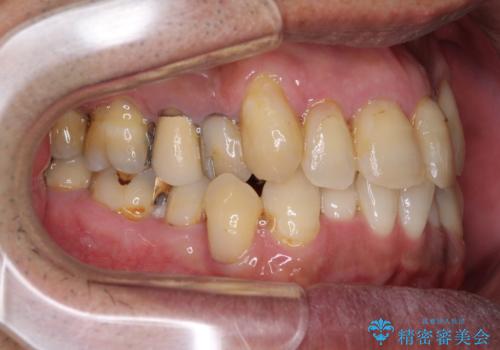

- 前歯がのデコボコや、奥歯に咬んだときに痛みがあるとのことで来院された患者様です。

全体的に問題が多く、全てをしっかりと治療したいとのことでした。

全体的に中等度の歯周病と診断されたため、歯周外科処置やインプラントによる咬合回復から進めて行き、矯正治療による歯列改善を行った後にオールセラミッククラウンにて補綴することとしました。